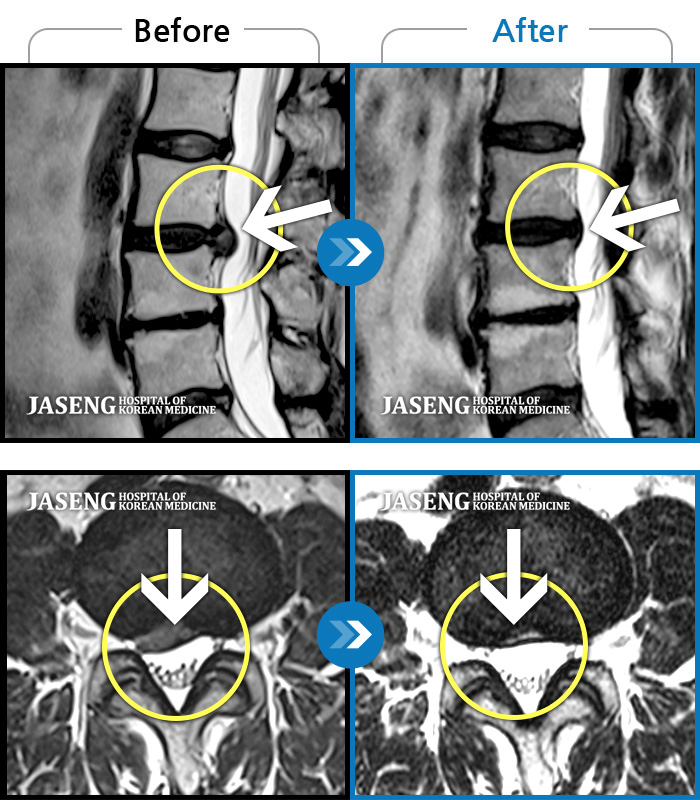

Before

After

허리통증이 심해서 숙이기 어렵고 차에서 내리기 힘들었습니다.

2021.01.06 ~ 2025.03.10